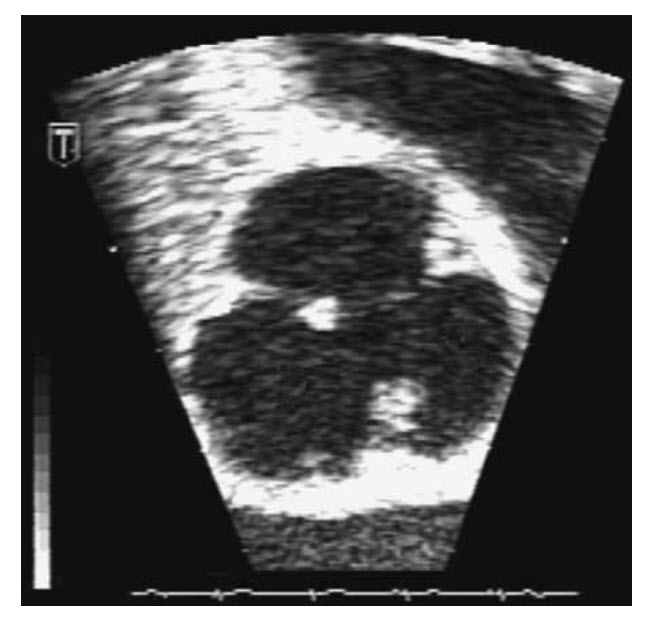

A 77-year-old female is seen 5 days after a right-sided ischaemic cerebrovascular event. There was a history of hypertension but no other significant cardiovascular risk factors. Examination revealed a resolving left hemiparesis and homonemous hemianopia. Cardiovascular examination was unremarkable. There were no peripheral stigmata of endocarditis. CRP was 17 and WCC 10.4. Urinalysis showed 1+ protein. Five days of cardiac monitoring showed sinus rhythm. A transthoracic echocardiogram is shown in Figure below

Which one of the following statements is correct?

Papillary fibroelastomas are rare, representing <10% of all primary cardiac tumours. Ninety per cent occur on the valves, but they have been reported to arise on the intima of the right coronary sinus, the ventricles, and the mitral valve apparatus. The majority (90%) are single, but multiple lesions have been described and are usually <1 cm in diameter. Left-sided fibroelastomas are more commonly reported than right-sided ones. Most patients are over 50 years of age. Clinical examination is typically unremarkable. The potential for fibroelastomas to cause serious complications has been increasingly apparent. Fibroelastomas of the left side of the heart have been associated more frequently with serious symptoms. Cerebrovascular symptoms have been described frequently and many of these patients have had multiple episodes. Some papillary fibroelastomas are congenital. However, most lesions are probably acquired. Some authors regard fibroelastomas as giant Lambl excrescences (Salyer WR), whereas others (McAllister and Fenoglio) regard them as true benign neoplasms. The risk of embolic phenomenon is not well correlated with the size of the structure and for this reason it is generally thought that even small fibroelastomas should be considered for surgical resection.